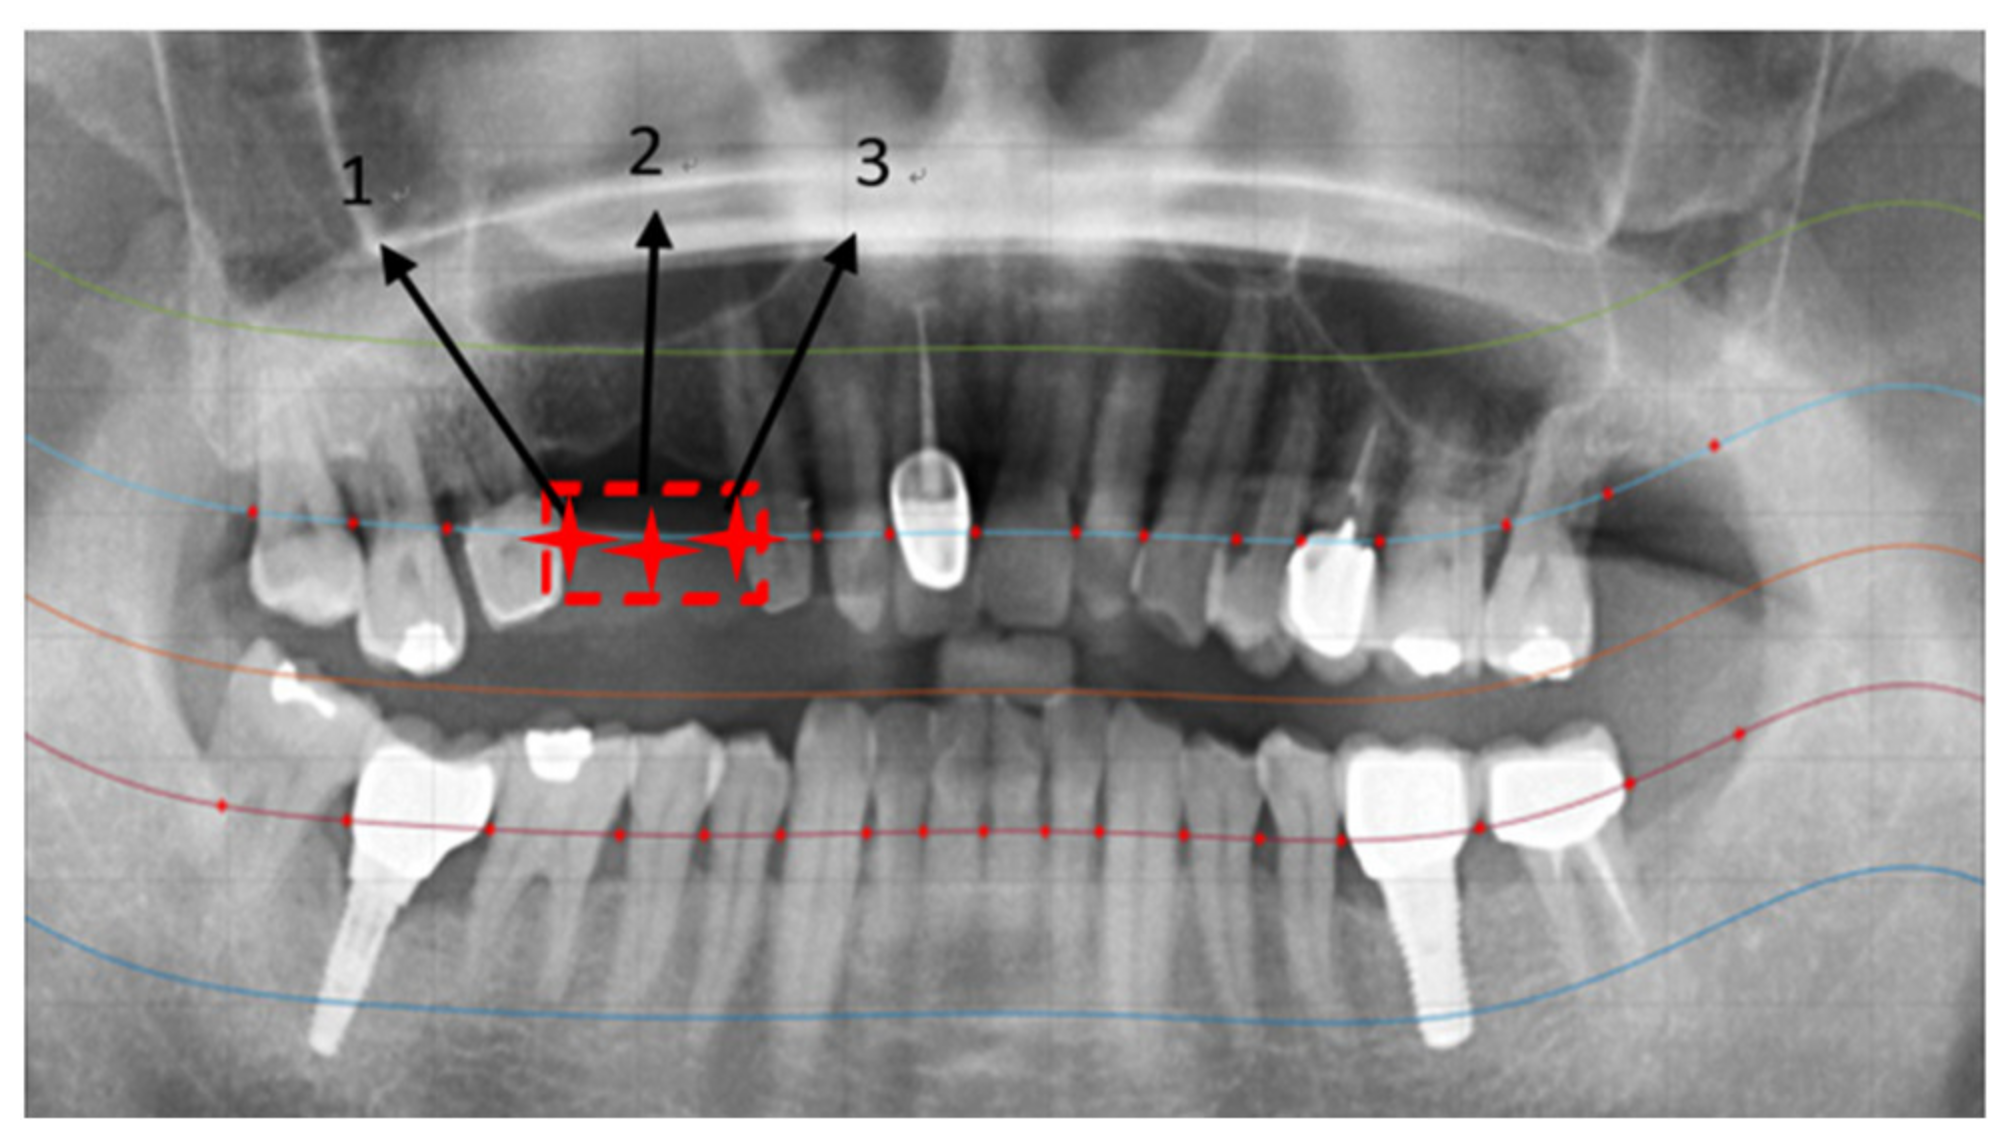

2.2.3. Positioning Numbers

3. Results